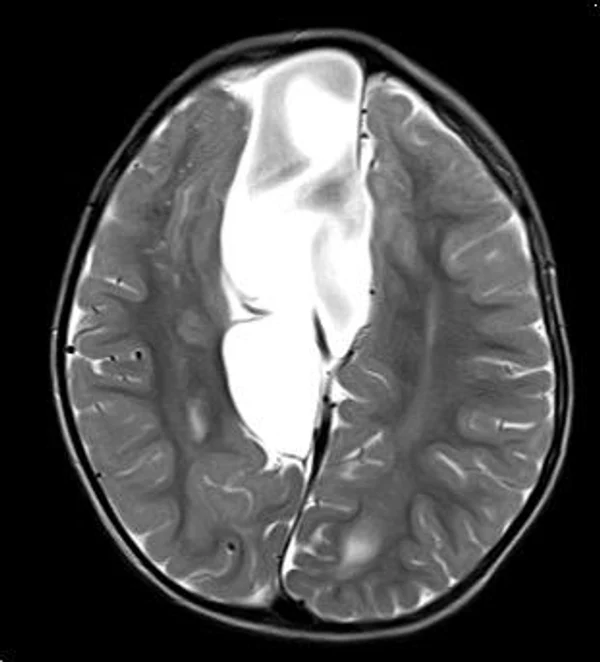

кисты, аномалии Денди-Уокера и др.Операции при внутричерепных кистах. В основном встречаются арахноидальные кисты различных локализаций и кисты сосудистых сплетений боковых желудочков. Пациентам с врождёнными кистами операции проводятся в следующих ситуациях: увеличении объема кисты в динамике, наличии клинических проявлений, компрессии и дислокации мозговых структур, наличии окклюзии ликворных путей. Нами используются 2 способа хирургического лечения кист: эндоскопическая перфорация стенок кист и открытая резекция кист. Открытая резекция кист проводится при ретроцеребеллярных арахноидальных кистах (рис. 2), при арахноидальных кистах межполушарной щели при отсутствии непосредственного контакта их стенок со стенками расширенных желудочков головного мозга и повторного увеличения кист средней черепной ямки после эндоскопической кисто-цистерностомии. Техника операции заключается в проведение краниотомии и максимальном иссечении стенок кист с созданием широкого сообщения кист с субарахноидальным пространством. Эндоскопические операции проводятся при арахноидальных кистах межножковой и пинеальной цистерн, арахноидальных кистах межполушарной щели при тесном контакте их стенок со стенками расширенной желудочковой системы (рис. 3), первично при арахноидальных кистах средней черепной ямки, а также при кистах сосудистых сплетений боковых желудочков. При арахноидальных кистах межножковой цистерны эндоскопически проводится перфорация стенок кисты, сообщая ее с просветом III желудочка и межножковой цистерной – эндоскопическая вентрикуло-кисто-цистерностомия (рис. 4). При арахноидальных кистах пинеальной цистерны проводится перфорация кисты в передне-верхних её отделах с созданием сообщения полости кисты с просветом III желудочка – эндоскопическая кисто-вентрикулостомия. С целью предотвращения облитерации сформированного отверстия иногда в полость кисты под контролем эндоскопа вводится стент перфорированный на протяжении (рис. 5, 6). Эндоскопическая кисто-цистерностомия выполняется при арахноидальных кистах средней черепной ямки. При этом создается широкое сообщение кисты с базальными цистернами. При кистах сосудистых сплетений боковых желудочков проводится их вскрытие в просвет боковых желудочков – эндоскопическая кисто-вентрикулостомия. При множественных кистах проводится их хирургическое сообщение между собой – интеркистосмия